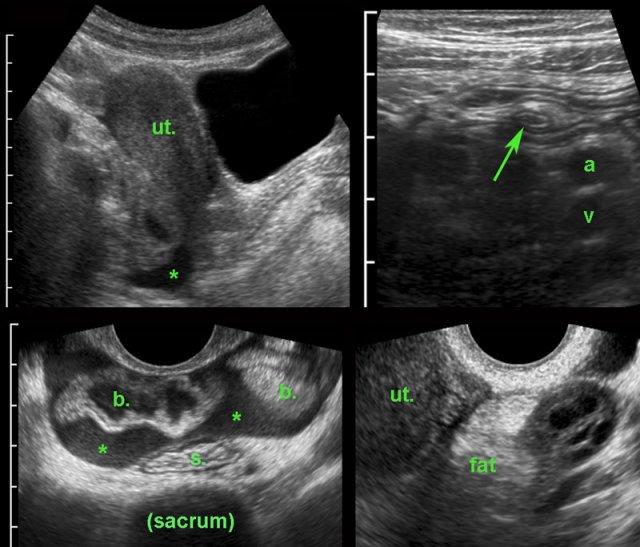

Tử cung và buồng trứng được quan sát rõ nhất khi bàng quang chứa đầy một nửa.

Bàng quang quá căng đầy gây khó chịu cho bệnh nhân, cản trở việc ép đầu dò đúng mức và đẩy các cơ quan ra xa thành bụng phía trước, làm hạn chế việc sử dụng đầu dò tần số cao.

Trên mặt phẳng đứng dọc có thể xác định được tử cung, cổ tử cung, âm đạo, trực tràng hậu môn và niệu đạo (u.), cũng như túi cùng trước và túi cùng sau của âm đạo ở trạng thái xẹp.

Nghiên cứu tử cung ở tư thế gập sau đòi hỏi bàng quang phải được làm đầy nhiều hơn.

Mặt cắt ngang cho phép quan sát cả tử cung

và buồng trứng.

Bản thân tử cung cũng có thể cung cấp

một cửa sổ âm học để quan sát buồng trứng.

Với tử cung ở tư thế gập trước, các buồng trứng nằm khá về phía bụng và thường có thể được quan sát bằng cách sử dụng các mạch máu chậu phải và trái làm cửa sổ âm học (hình).

PID giai đoạn sớm với ruột thừa dày thứ phát. (ut. = tử cung, b = ruột non, a và v = động mạch và tĩnh mạch chậu, s = đại tràng sigma)